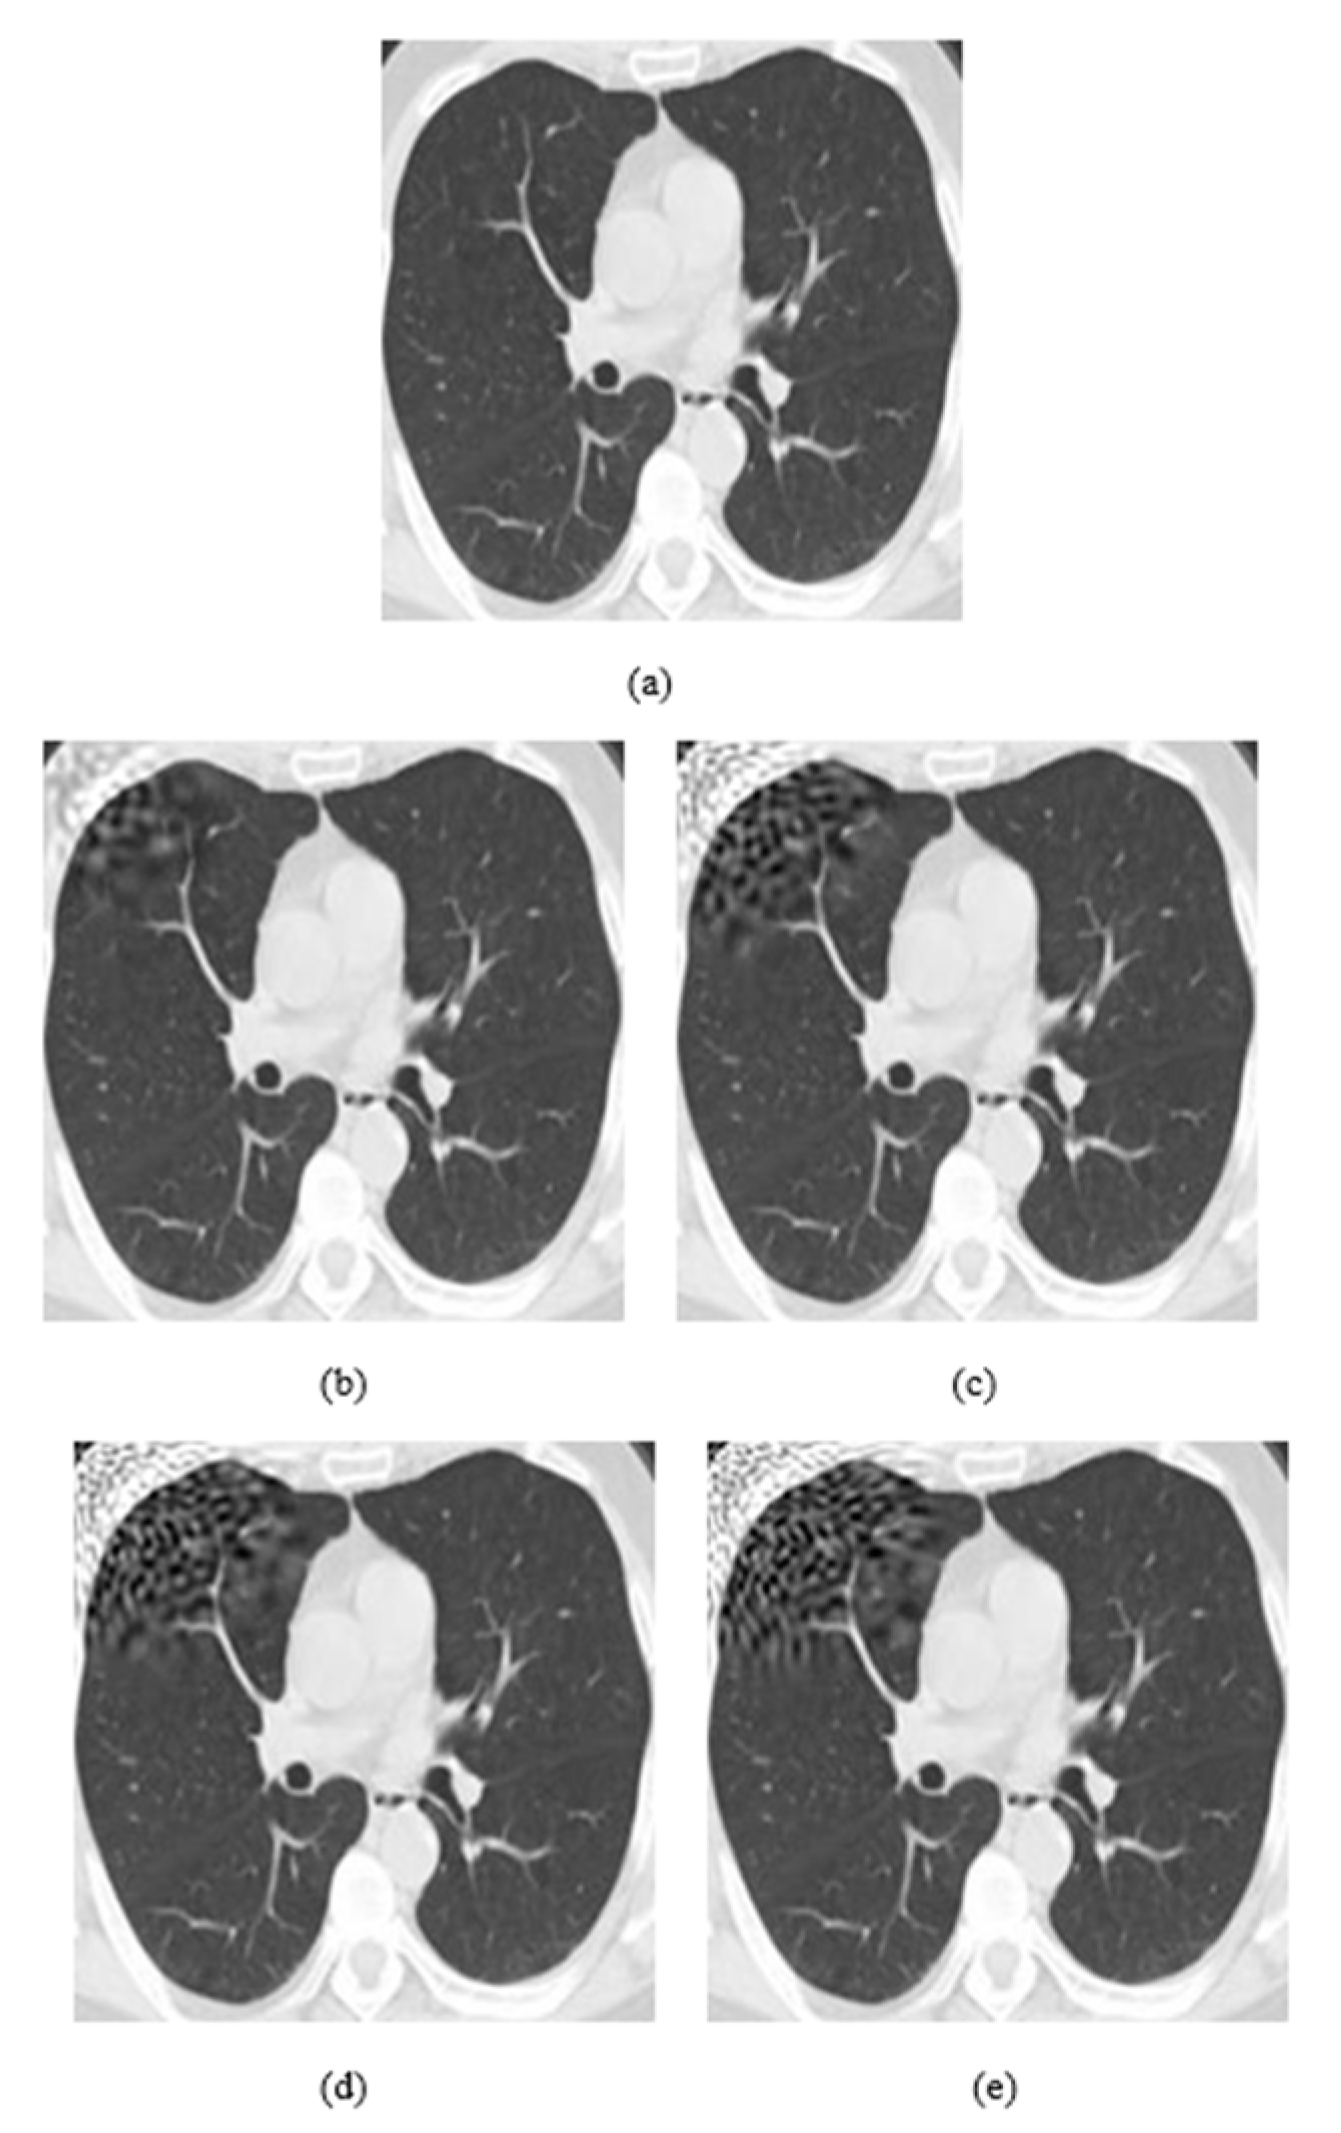

Figure 5.

(a) Initial image, (b) L-bit = 200, (c) L-bit = 500, (d) L-bit = 800, (e) L-bit = 800. The rest parameters are Embedding strength = 300, p1 = 0.1, p2 = 0.1.

As it is depicted in Figure 4, increasing the embedding strength the quality of the image is getting worse and the noise becomes more perceptible and intense. On the other hand, in Figure 5 the intense of the noise is almost the same in all L-Bit lengths, but it changes the magnitude of the noise.